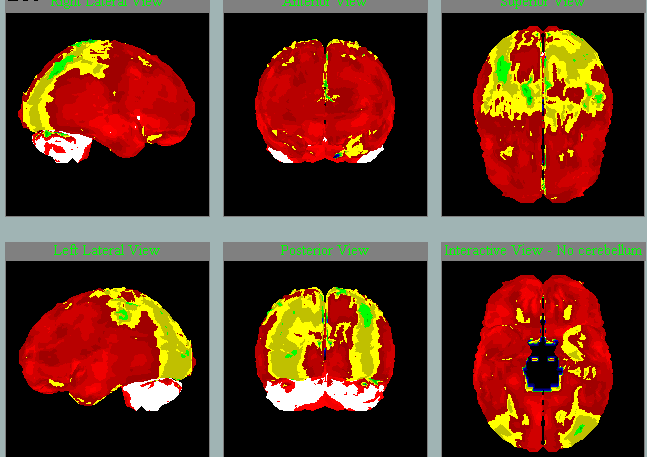

Oproti jiným pomocným metodám SPECT mozku je levný, prakticky neinvazivní a snadno dostupný v každé větší nemocnici. Vyšetření se dá zpracovat do trojrozměrného mozku pomocí speciálního programu NeuroGam. Tato metodika přináší důležité informace týkající se prostorového zhodnocení korové perfúze. Hypoperfúzní oblasti jsou jasně barevně odlišeny od normálního prokrvení, protože se výsledek porovnává s dostupnou normálovou populací. Perfúzní vzorce mohou v některých případech významně napomáhat správné diagnostice, a to lépe než strukturální CT / MR mozku, kde je vidět úbytek tkáně až později. O klinickém přínosu SPECT mozku je možné se dozvědět ve 14minutové přednášce.

Různé nemoci na SPECT mozku s charakteristickými vzorci hypoperfúze

Frontotemporální lobární degenerace

Pedevším temporální hypoperfúze vlevo.

Především frontální hypoperfúze oboustranně.

Především frontotemporální hypoperfúze vlevo.